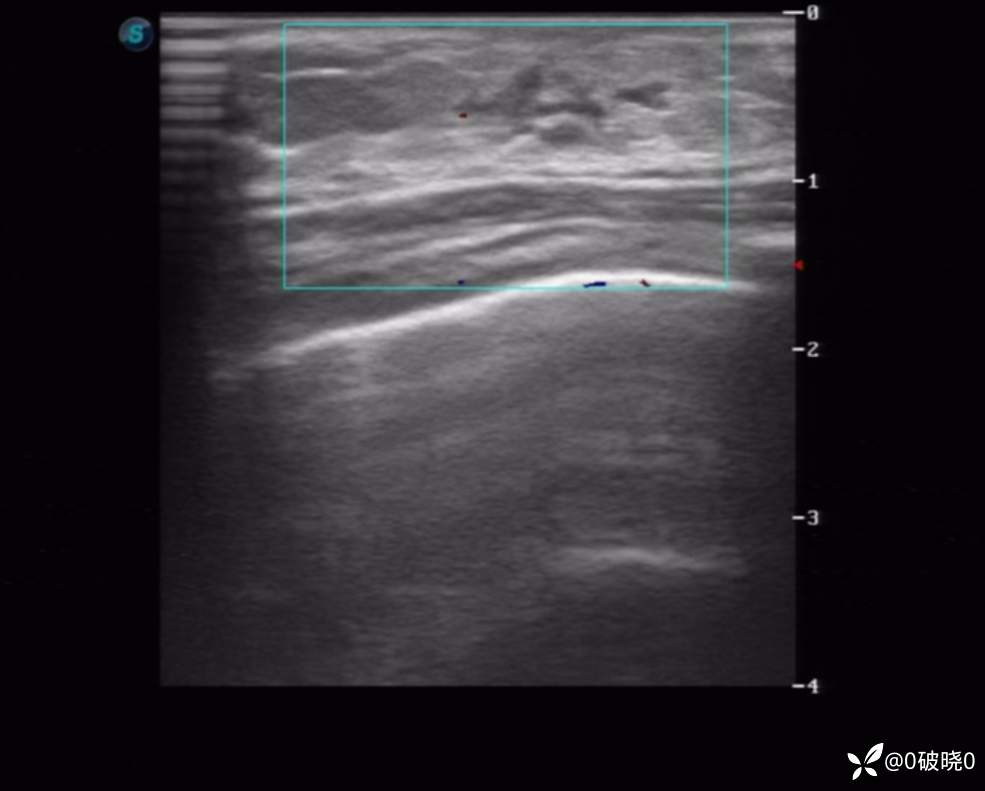

女童,7岁,9天前突感乳头处疼痛,当时家长触及到花生米大小的结节,9日后发现结节长大至2cm,但疼痛减弱,遂来诊。超声显示:包块处呈腺体样回声,其内回声不均,可见不规则低回声及团样高回声区,其旁可见细管样回声。CDFI:其内可见点、条状动脉血流信号。